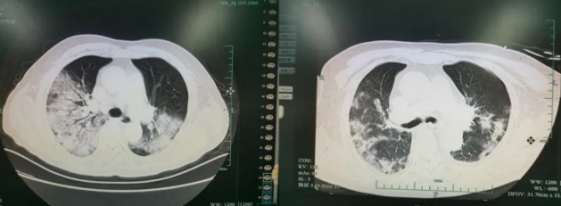

白肺有什么樣的癥狀?哪些情況下會引起白肺?胸外科專家來告訴你在我們的生活中,健康問題總是層出不窮,而有些疾病因為它們的隱蔽性和復雜性,常常在被發現時已是晚期。白肺就是這樣...